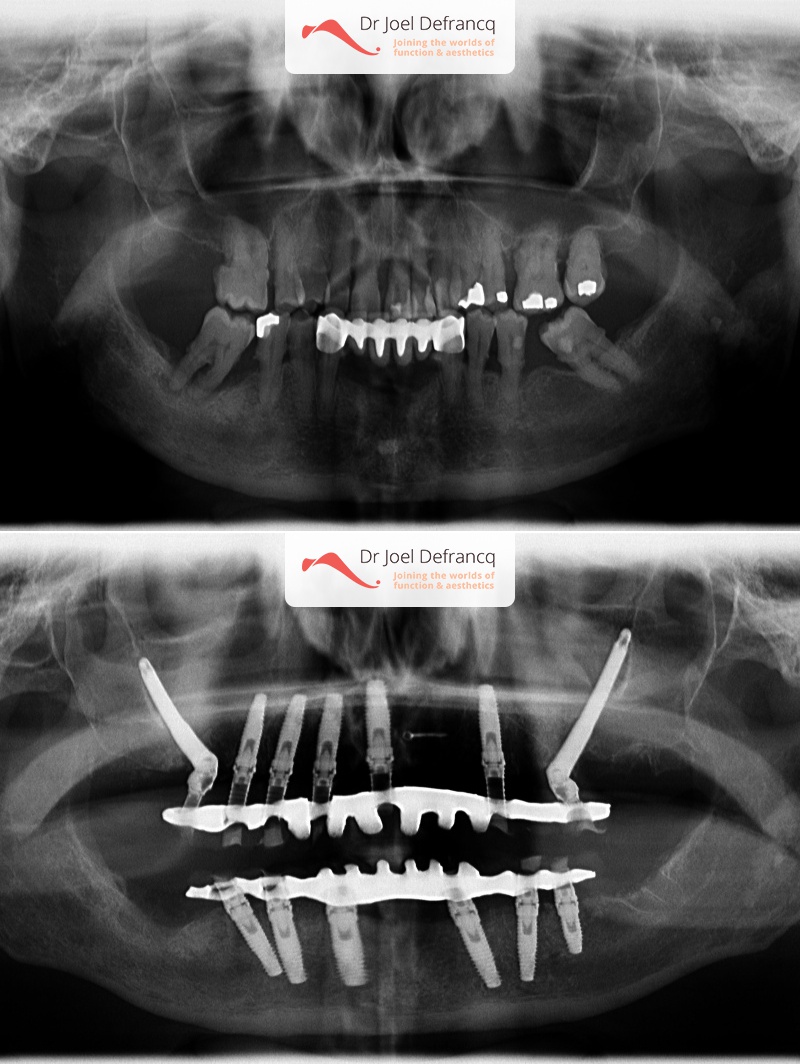

Virginie: Implantaten "all-on-4 four" concept

Diagnose van het gezicht

- Slechte tanden

Behandeling tandheelkundige implantaten

- Vaste tanden op implantaten (bovenkaak)

- Vaste tanden op implantaten (onderkaak)